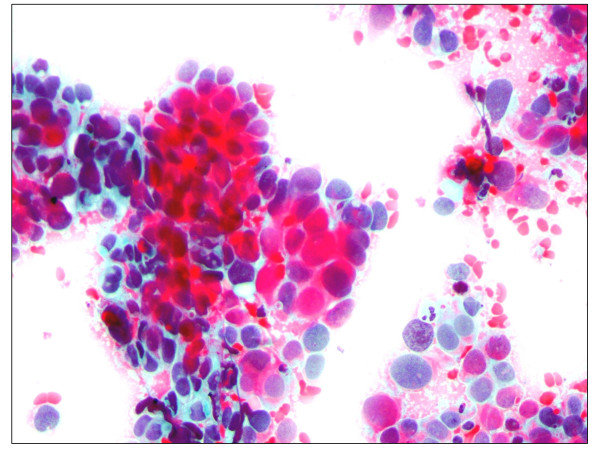

Positive control sample 3, from validation dataset (external).

Successfully classified as risk: 0.061